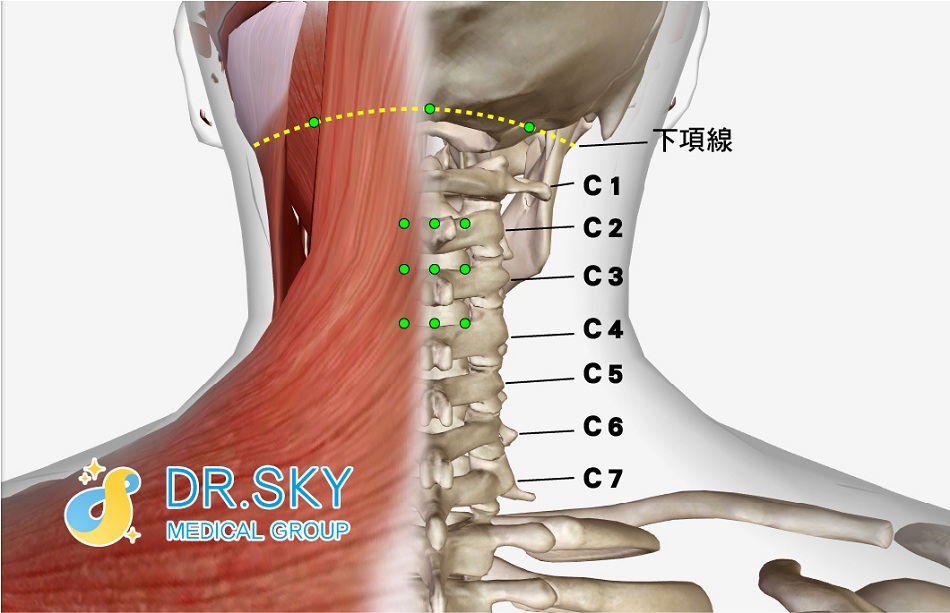

當頸椎上段的軟組織受到損傷,枕頸筋膜勞損、攣縮還有小關節錯位,因頸椎內外平衡失調,解剖位置改變,這些因素都會使頸部相關力學壓力結構發生改變,原本附著在壓力結構上的感應系統即會發出「警告訊號」產生耳鳴,這才是造成頸源性耳鳴的主因!而這個壓力結構主要的組成正是人體的筋膜系統。

▲ 頸部筋膜系統示意圖

▲ 頸源性耳鳴治療部位